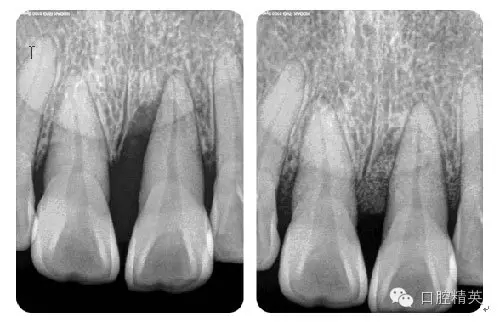

病例7:根尖切除術(shù)

病例8:牙周植骨術(shù)